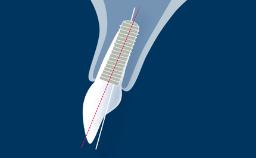

This module will define risk factors, both systemic and local, in relation to implant therapy as well as relative and absolute contraindications to implant placement.

- identify risk factors associated with implant therapy

- identify the local risk factors associated with implant therapy